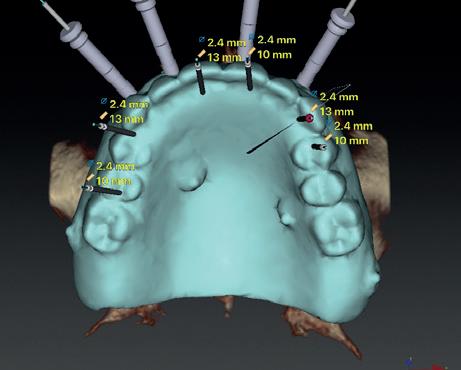

Voor het implantologisch onderzoek werd een CBCTscan (Trium CBCT, Acteon Frankrijk) vervaardigd van de edentate bovenkaak en in de software werd een planning gemaakt van 6 implantaten in de bovenkaak. De kaak kan opgedeeld worden in het front, tussen de 13 en 23 en de zijdelingse delen van de 14 t/m 17 en 24 t/m 27. Er dienen 2 implantaten in het front geplaatst te worden en 2 implantaten in de zijdelingse delen rechts en links, om een optimale verdeling van de implantaten (implant spread) te krijgen. De implantaten in deze casus werden gepland op posities 12, 22, 14, 24, 16 en 27. Tevens werd rekening gehouden met de krachtenverdeling óp de implantaten, deze zijn naar dorsaal toe forser dan in het front, daarom werd er gekozen voor brede implantaten (meer dan 5.0 mm in diameter) distaal en 4.0 mm diameter implantaten in het front. Voor de 16 was een crestale sinusbodemelevatie nodig en de 14 benodigde een kaakverbreding en verhoging.

Om de implantaten op de juiste vooraf geplande positie te implanteren, zijn er een aantal mogelijkheden (afbeelding 1 en 2). Eén daarvan is om de chirurgie guided uit te voeren, maar dat is lastig omdat de guide niet op elementen afgesteund kan worden. De guide dient dan met guide pins vastgeschroefd te worden, maar dat heeft als nadeel dat bij verplaatsing van de guide de implantaten niet op de juiste positie staan. Bij immediaat implanteren kan tegenwoordig gebruikgemaakt worden van meerdere stac-

1. Edentate maxilla

2. Planning in de CBCT-software Acteon AIS

kable guides, die op een base guide geklikt kunnen worden. Een tweede methode is om op basis van de CBCT-scan in de mond uit te meten waar de implantaat locaties zijn en door te kijken naar referentie van de onderkaak. In deze cases werd besloten om de implantaten vrij uit de hand te plaatsen.